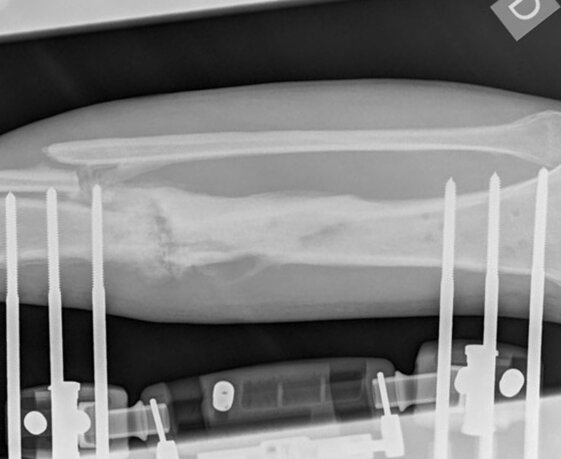

Controllo radiologico ad un mese dall’inizio della terapia. La fistola si è chiusa.

L’esame RX dimostra la formazione di callo osseo, prevalente dal lato opposto all’inserzione dei fissatori esterni e i segni di consolidazione del focolaio di pseudoartrosi.